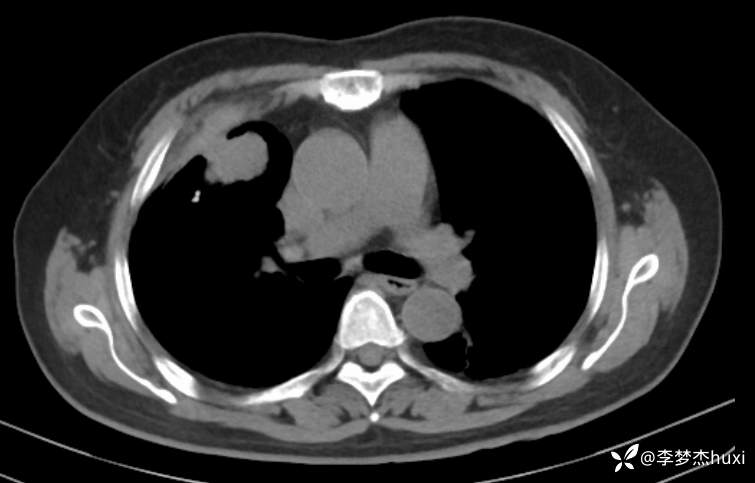

辅助检查:胸部CT:右肺占位?炎症?双肺炎性变,左肺下叶陈旧性病变,双肺纹理增多,主动脉及冠状动脉钙化,双侧胸膜局部增厚,胆囊结石,多发肝囊肿?请结合超声。

临床诊断:肺占位